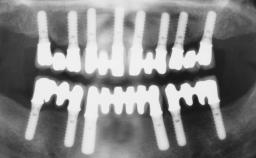

Immediate Loading of Six Implants in the Maxilla and Final Restoration with a Full-Arch CAD/CAM Zirconia FDP

A 63-year-old male patient was referred for a consultation and treatment of partial edentulism in the maxilla. The patient presented with residual anterior teeth and declined a partial removable prosthesis. He reported that the maxillary posterior teeth had been extracted due to mobility and periodontal disease two months before the consultation. The patient’s chief complaint was that his residual maxillary teeth were mobile and that he was unable to chew. The patient’s desire was a stable and comfortable fixed maxillary rehabilitation. The patient was a light smoker (fewer than 10 cigarettes/ day), and his medical history was without significant findings. He was not on any regular medication at the time of consultation. The extraoral examination revealed a normal physiognomy with a correct distribution of the facial thirds. The patient presented a low lip line, and the transition line between teeth and soft tissues was not exposed during a forced smile.

# of Implants 6

Type of Implants One-Piece